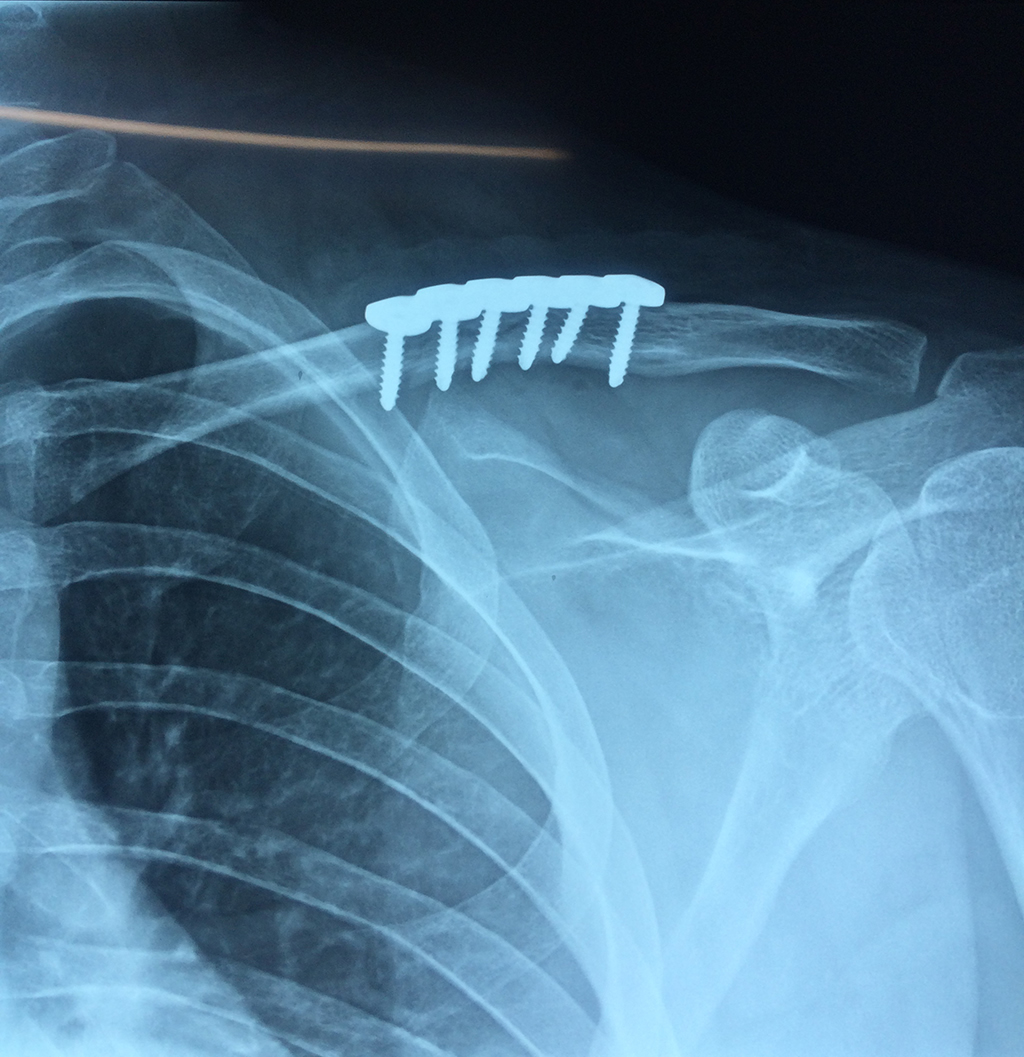

Calcaneo - Clavícula

La clavícula es un hueso largo, con forma de "S" itálica, situado en la parte anterosuperior del tórax. Junto con la escápula forman la cintura escapular. Se puede palpar por toda su longitud y se extiende del esternón al acromion de la escápula, siguiendo una dirección oblicua lateral y posterior.